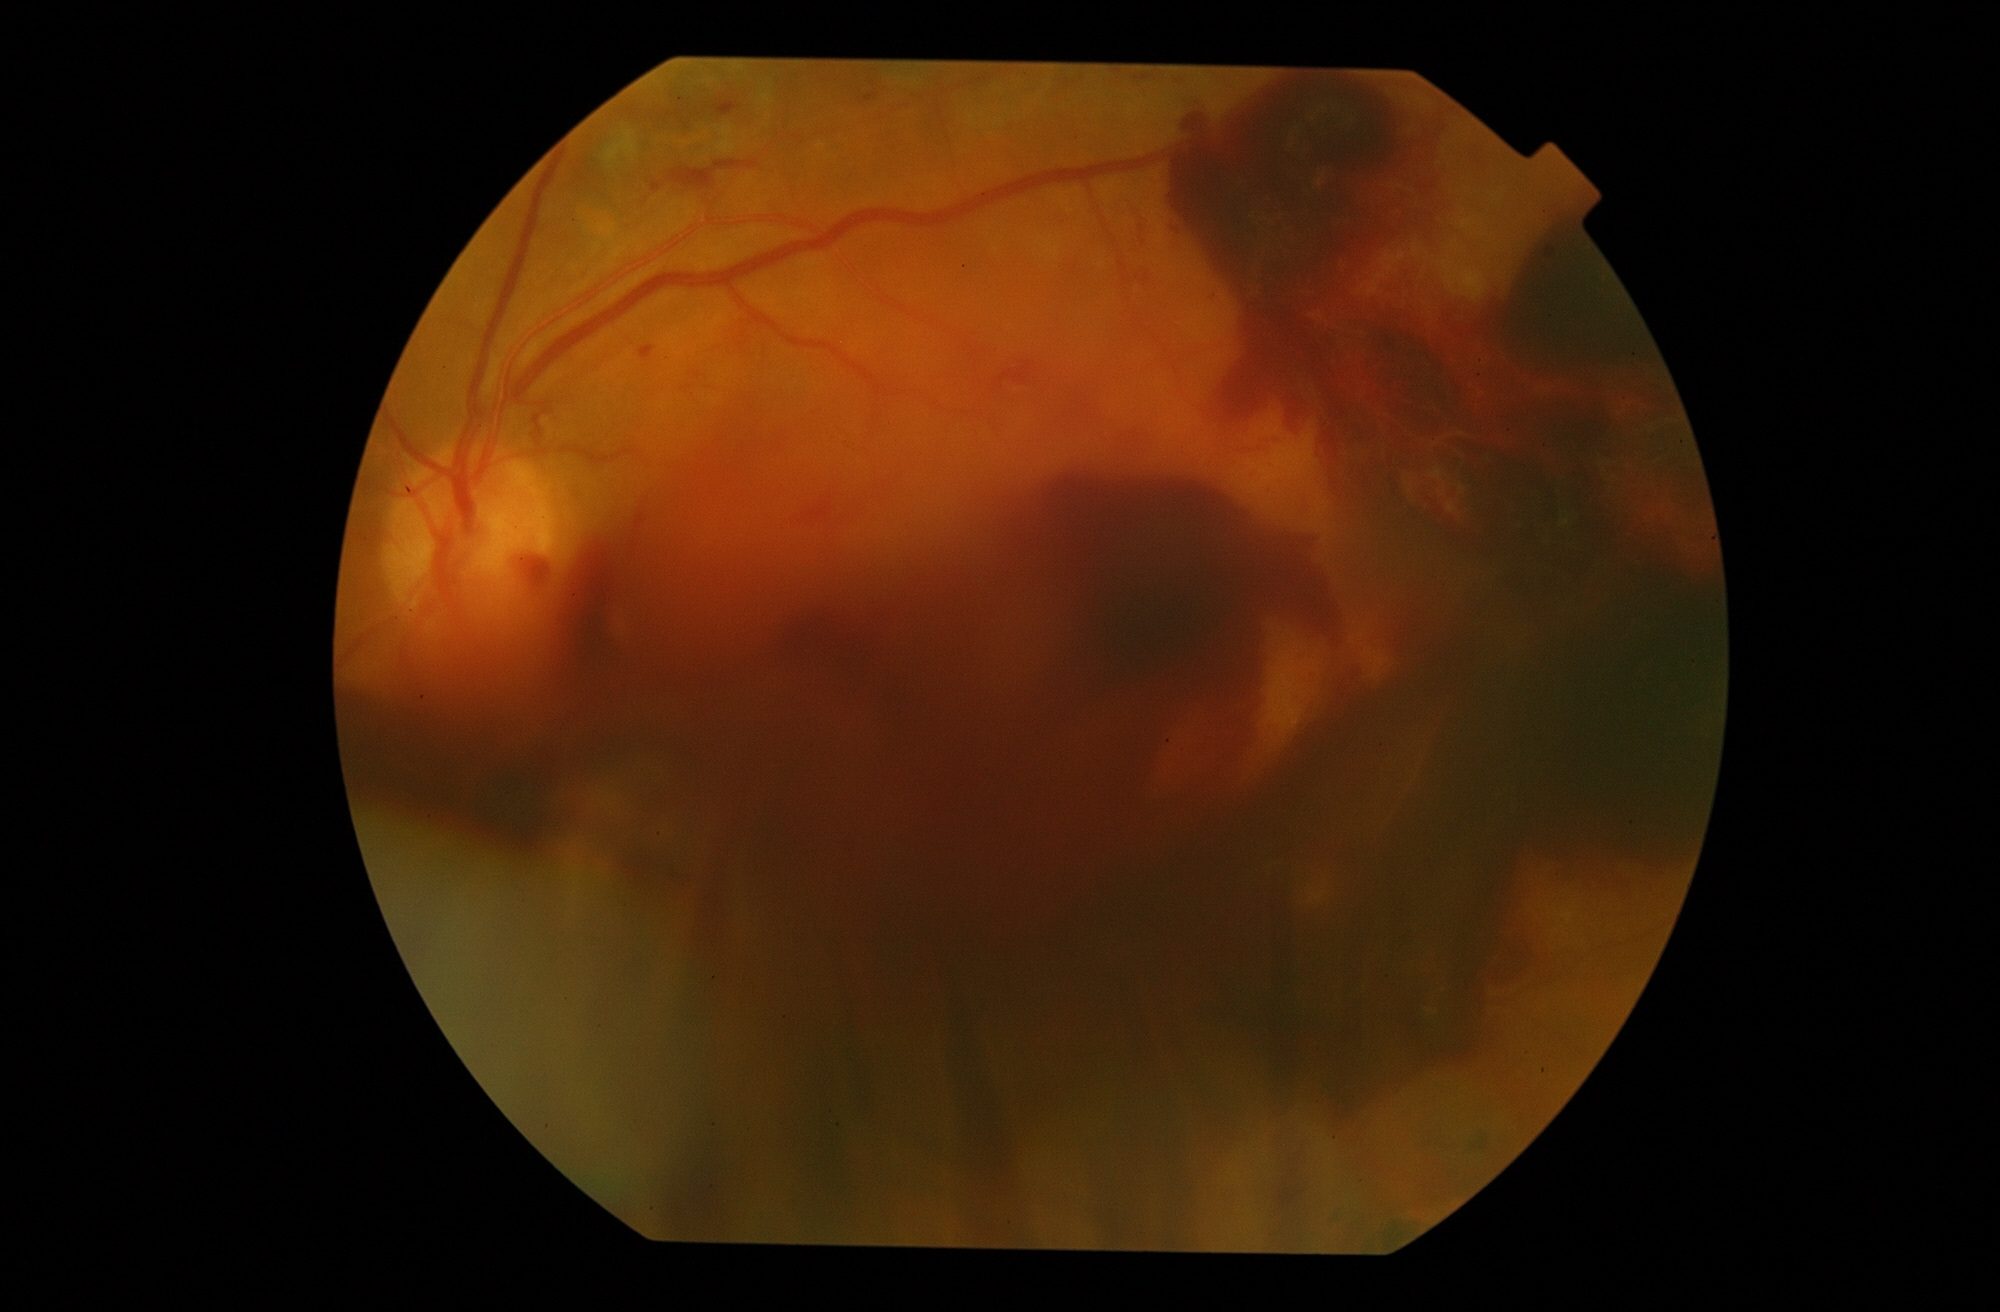

¿Que es la Retinopatía Diabética? La Retinopatía Diabética es un de las principales causas de pérdida de visión en los adultos.

→ Leer más